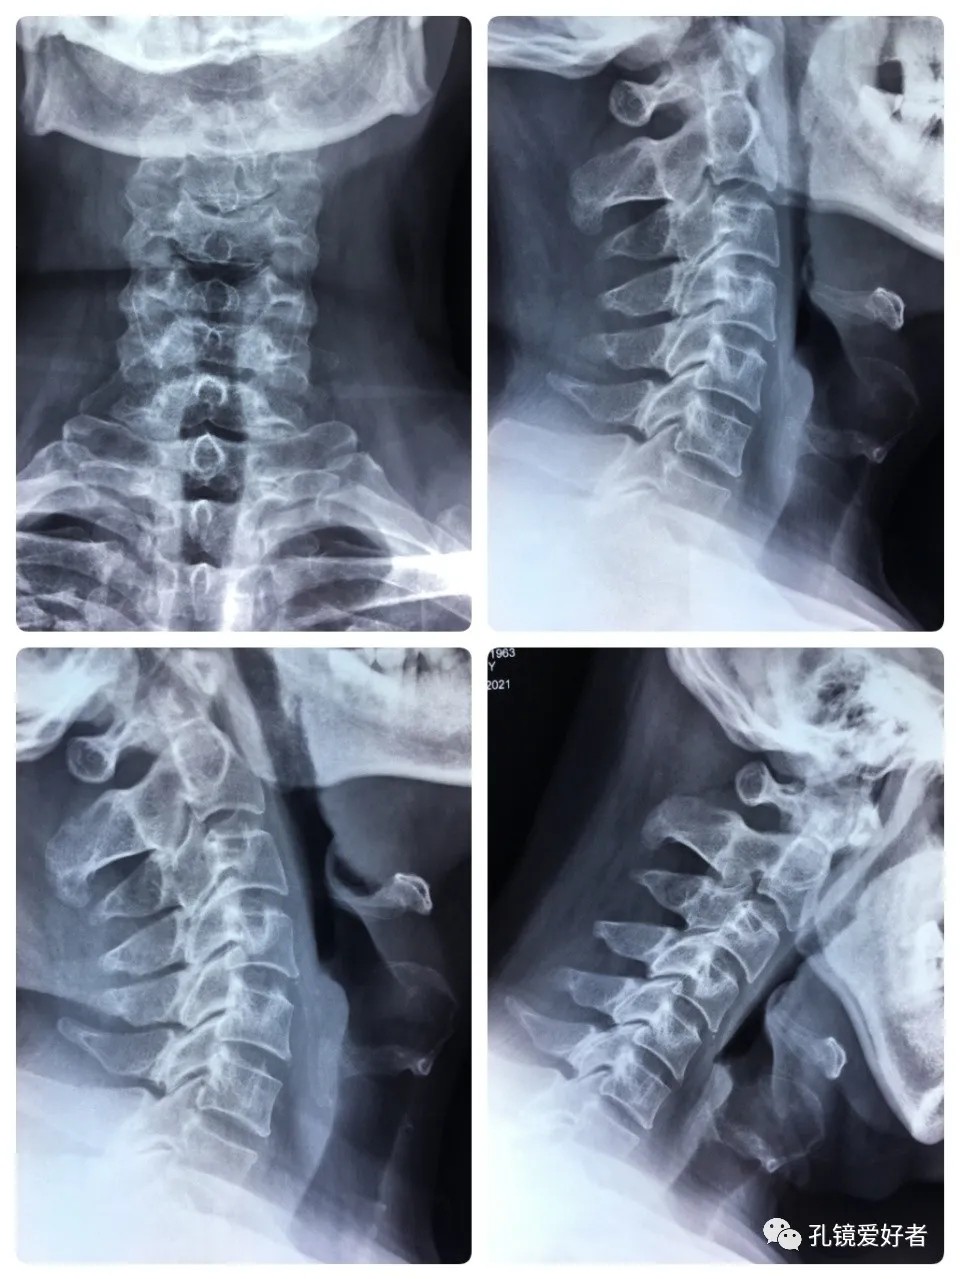

The patient's preoperative imaging data

The PA and lateral and flexion-extension position of cervical spine